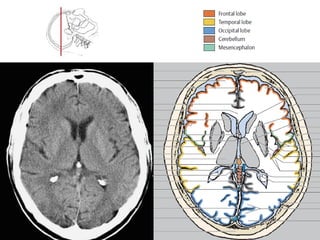

Read the information on the CT scan Do not get disoriented Hold the film in the proper orientation Follow the IV contrast filled Aorta as we descend caudally. CT scans of the mediastinum are reconstructed filmed and interpreted in an axial format. The mechanism is based on a quickly rotating narrow beam of x-rays directed towards a patient that produces signals that are processed by the machines software.